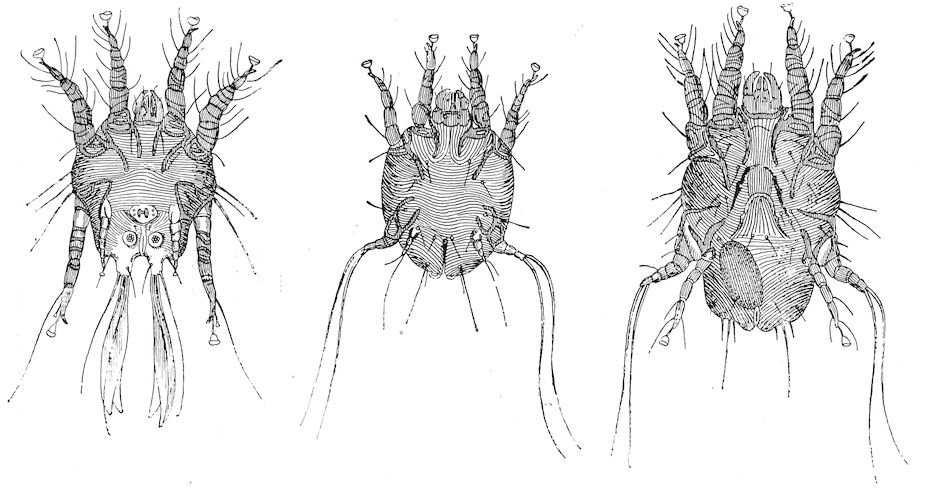

| II. | PHTHIRIASIS | 608 | ||

| Scabies—Scab—Mange | 611 | |||

| Scabies in sheep | 611 | |||

| Sarcoptic scabies | 612 | |||

| Psoroptic mange—Sheep scab | 614 | |||

| Chorioptic mange—Symbiotic mange—Foot scab | 636 | |||

| Mange in the ox | 638 | |||

| Sarcoptic mange | 638 | |||

| Psoroptic mange | 639 | |||

| Chorioptic mange | 640 | |||

| Mange in the goat | 641 | |||

| Sarcoptic mange | 641 | |||

| Chorioptic mange | 642 | |||

| Mange in the pig | 642 | |||

| Demodecic mange | 643 | |||

| Demodecic mange in the ox | 644 | |||

| Demodecic mange in the goat | 644 | |||

| Demodecic mange in the pig | 644 | |||

| Non-psoroptic forms of acariasis | 645 | |||